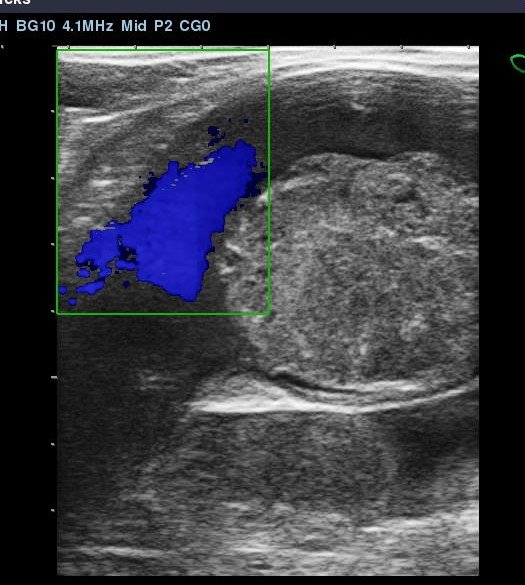

Diagnosis of this condition was confirmed by scanning the iliac arteries using transrectal ultrasound imaging. Normally the arteries are wide and uniform in cross section and the blood flow can be clearly seen. In the ultrasound images below, the dense grey structure within the vessel is the thrombus. The colour image is achieved using doppler to capture the blood flow and shows how the thrombus is partially occluding the artery.

A large thrombus within the iliac artery

This horse actually had a thrombus in the left and right iliac artery which is very unusual.